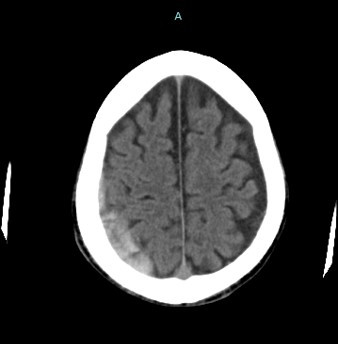

頭部CT:最も重要な検査であり、血腫の場所、大きさ、形状などを確認する。

MRI:頭部CTよりも詳細な画像が得るために行う。